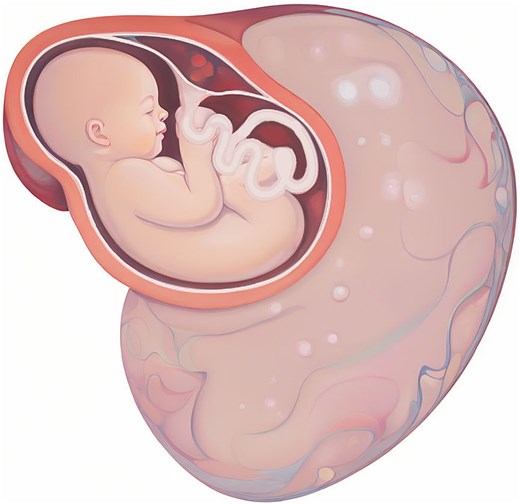

Illustration of the giant ovarian cystic mass position according to the uterus.